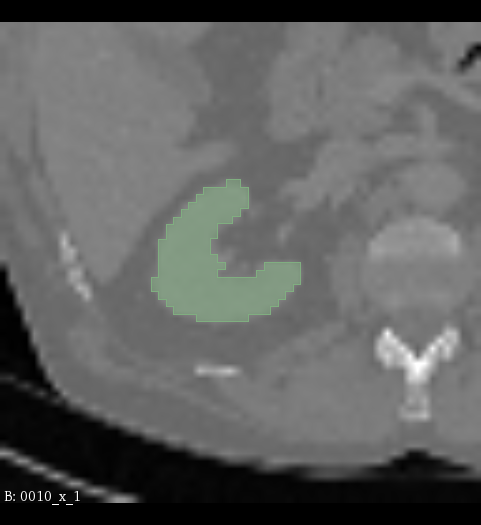

Figure 2: Illustration of the data from the TotalSegmentor data set [32] used in the experiments. The first row shows the axial, coronal and sagittal views passing the center of mass of the kidney in one of the data points. The second row shows the axial, coronal and sagittal views passing the center of mass of the aorta in one of the data points. The third row shows the axial, coronal and sagittal views passing the center of mass of the esophagus in one of the data points.

The experiments are conducted with respect to the TotalSegmentor data set [32]. This data set contains 1204 CT images with 104 anatomical structures (27 organs, 59 bones, 10 muscles, 8 vessels). To illustrate the effect noise may have on organs with different shape, three different organs are chosen. This includes the right kidney which in general is pretty spherical, the aorta which is tubular and relatively thick and the esophagus which is tubular and relatively thin. For each of the organs, 400 cases is selected and split into 5 folds of 80 cases. Finally, the images are sub-sample to half resolution and patches of 643superscript64364^{3} voxels centered in each of the structures are extracted.